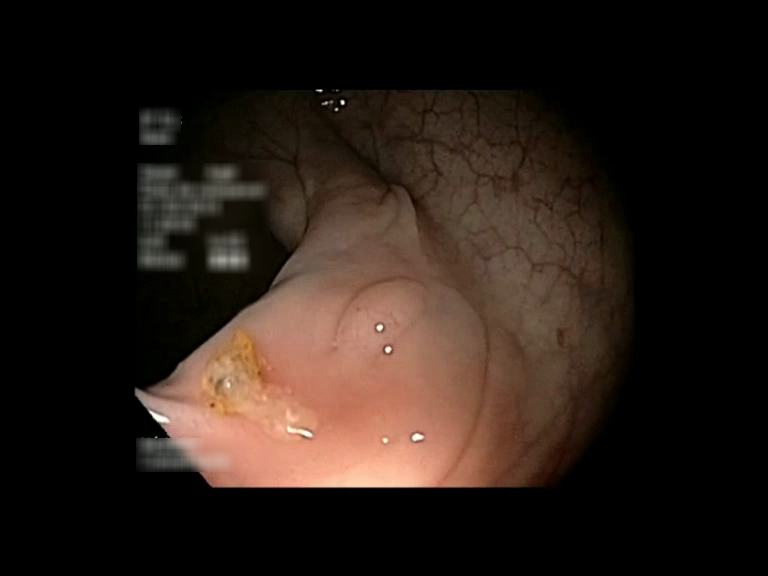

| Lesion | White Light Frame | NBI Frame | White Light Video | NBI Video | Camera Calibration |

| hyperplasic_01 |  |

|

WL.mp4 | NBI.mp4 | cam.xml |